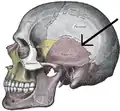

Side view of the skull. Squamosal suture indicated by the black arrows.

The squamosal suture, or squamous suture, arches backward from the pterion and connects the temporal squama with the lower border of the parietal bone: this suture is continuous behind with the short, nearly horizontal parietomastoid suture, which unites the mastoid process of the temporal with the region of the mastoid angle of the parietal bone. The term parietotemporal suture may refer to both of these sutures or exclusively to the parietomastoid suture and its use is, therefore, best avoided.